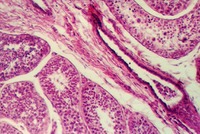

The Prostate epithelium looks cuboidal or pseudostratified low columnar in spots. Inside the glandular lumena you may see laminated bodies known as concretions. These are evident in the following photograph and help identify the organ as the prostate.

In the connective tissue there are bundles of smooth muscle which stand out

because of their homogeneous cytoplasm. Find smooth muscle in the above photograph

or the one below. What components of semen are contributed by the prostate?